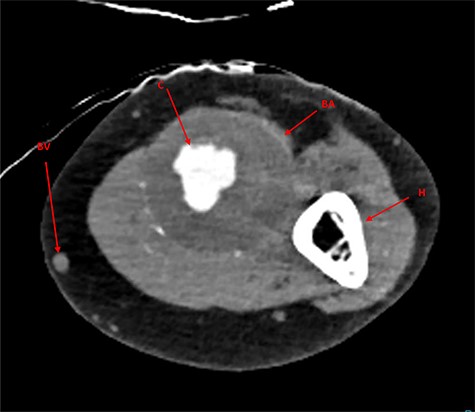

Examination revealed an expansive, pulsatile swelling over the whole upper arm. Ultrasound revealed the proximal axillary artery to be 10 mm, increasing to 14 mm below the axilla. The aneurysm measured at 45 mm diameter, decreasing to 16 mm above and 14 mm below the elbow. Significant thrombus was found within the aneurysm, but no distal embolization. The radial artery was small and the ulnar of normal calibre. A computated tomography angiogram (CTA) was arranged for surgical planning (Fig. 1).

CTA imaging of brachial artery aneurysm of the left arm; BA, brachial aneurysm; BV, basilic vein; C, contrast through aneurysm lumen; H, humerus.